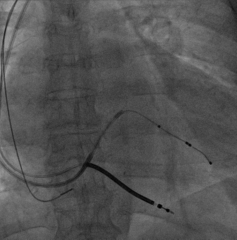

依次植入右室除颤导线(6935M-DF4)和右房导线(4574),均测试满意,分别固定。

关键一步,鞘中鞘和递送鞘管的切除,均比较顺利,电极无移位。

AP

LAO45

RAO30

固定左室电极,连接CRTD(DTBC2QQ),手术最终影像